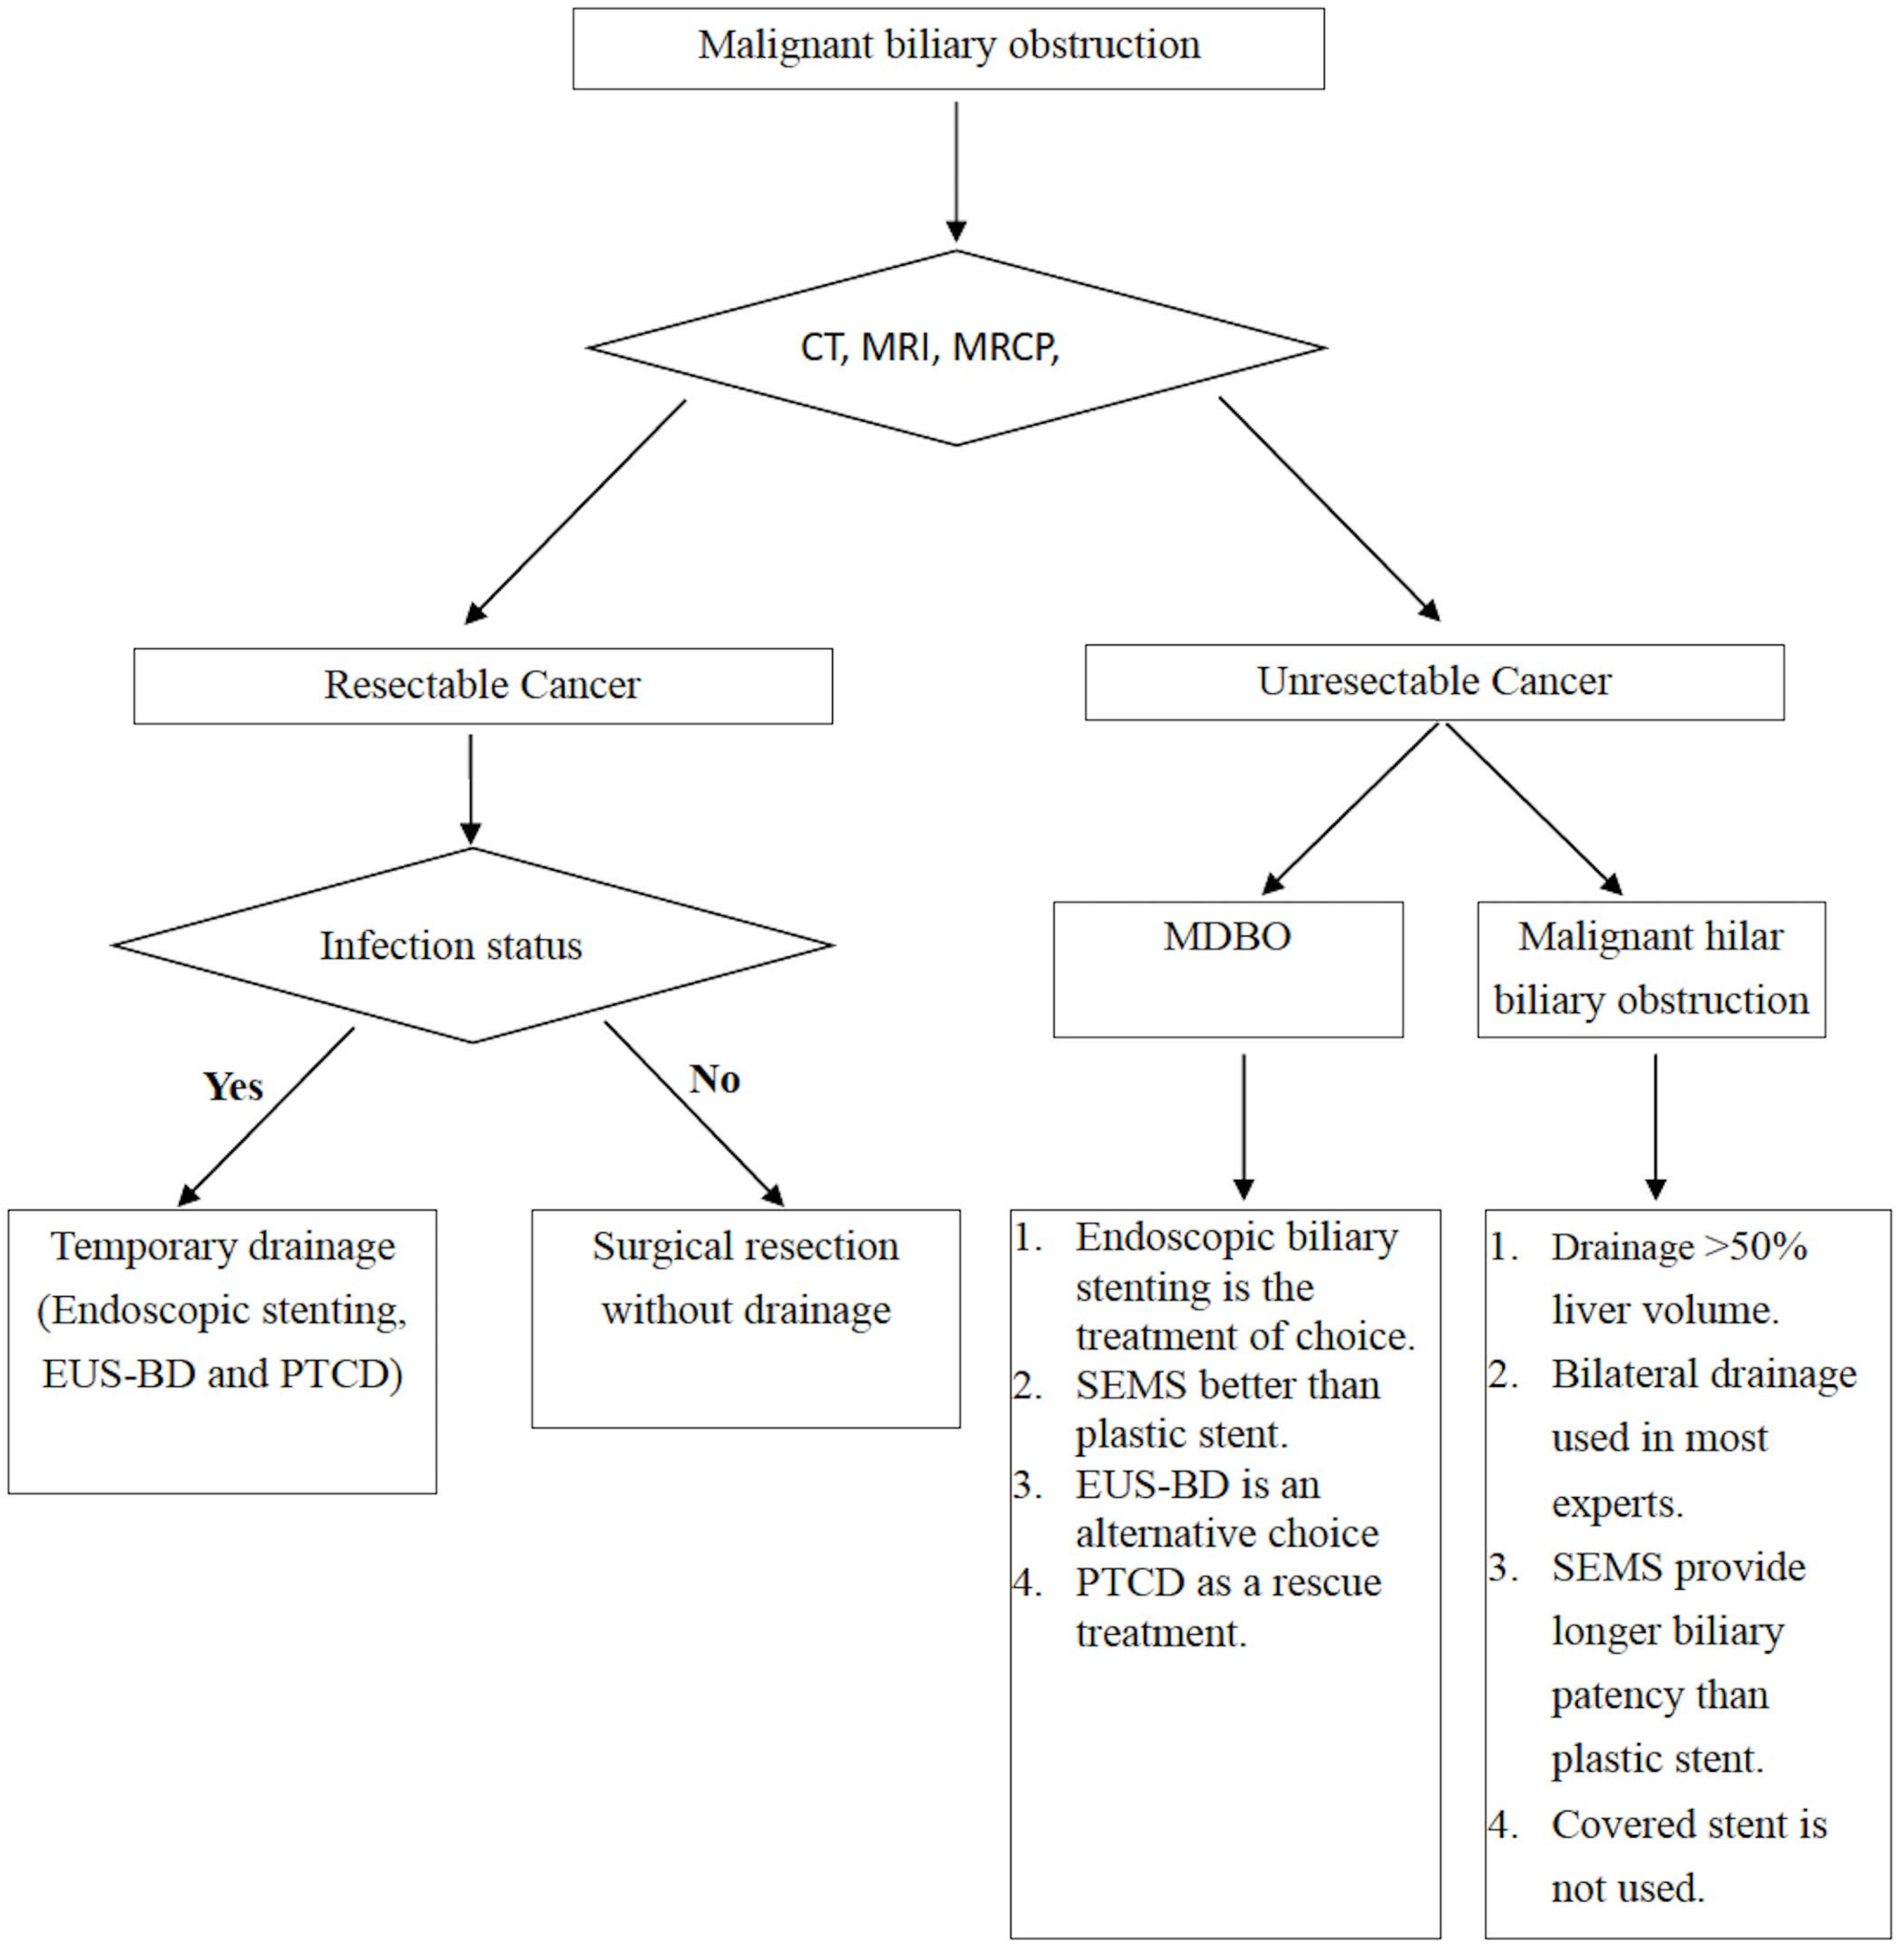

2. Resectable Malignancy

3. Unresectable Malignancy

3.1. Malignant Distal Biliary Obstruction

4. Malignant Hilar Biliary Obstruction

4.1. Bilateral or Unilateral Drainage

4.2. Stent Selection